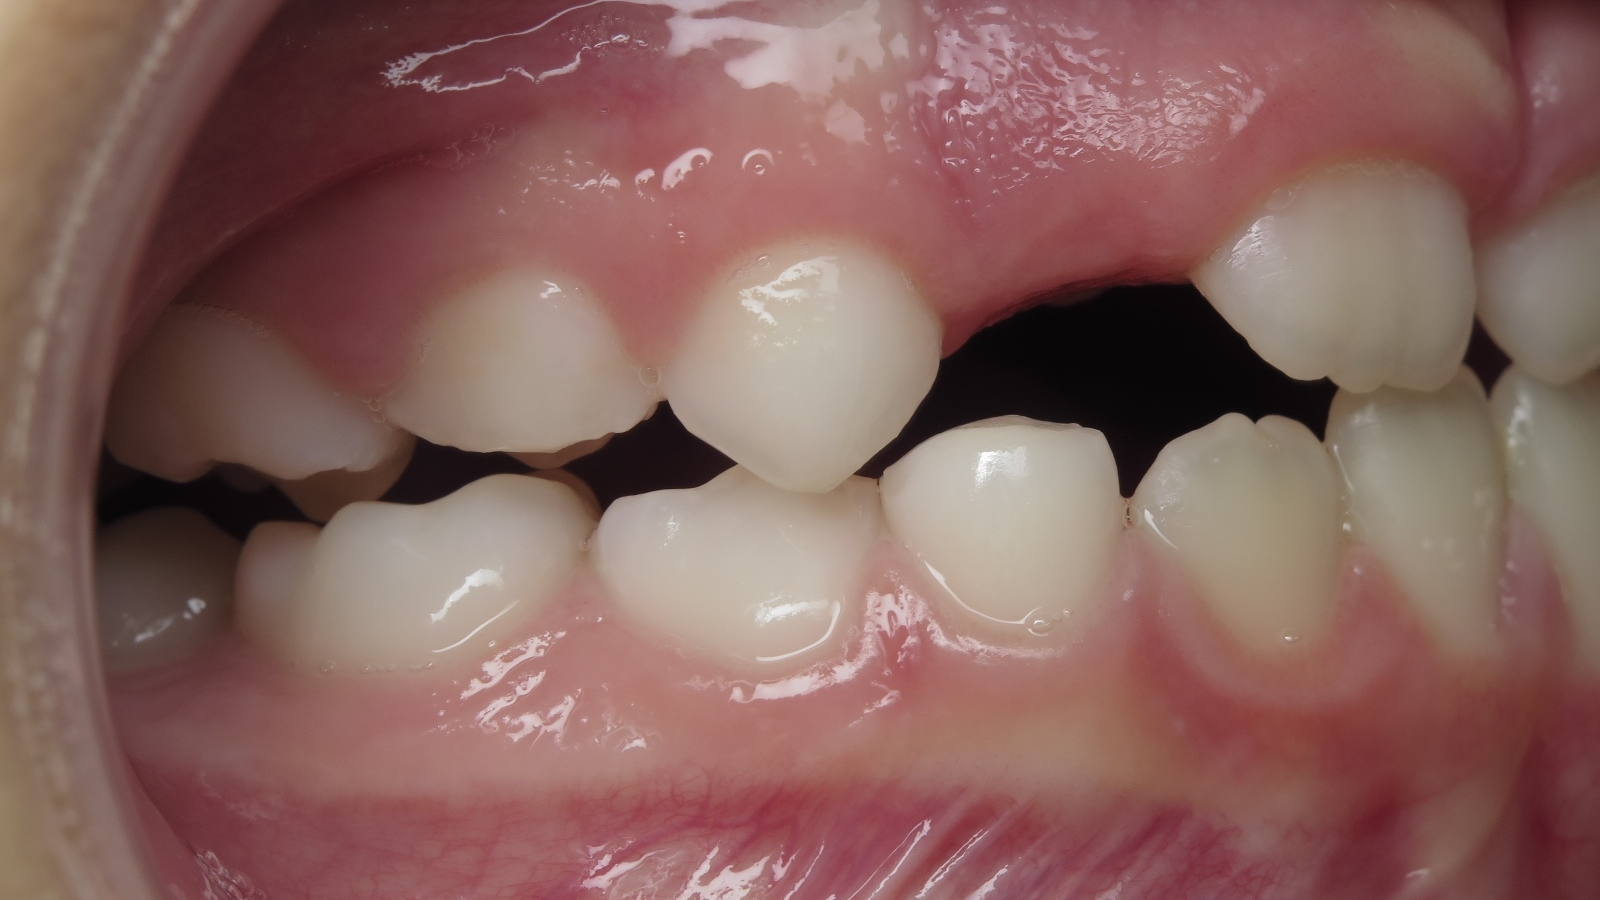

appareillage mobile pendant 22 mois

surveillance évolution de la dentition en cours